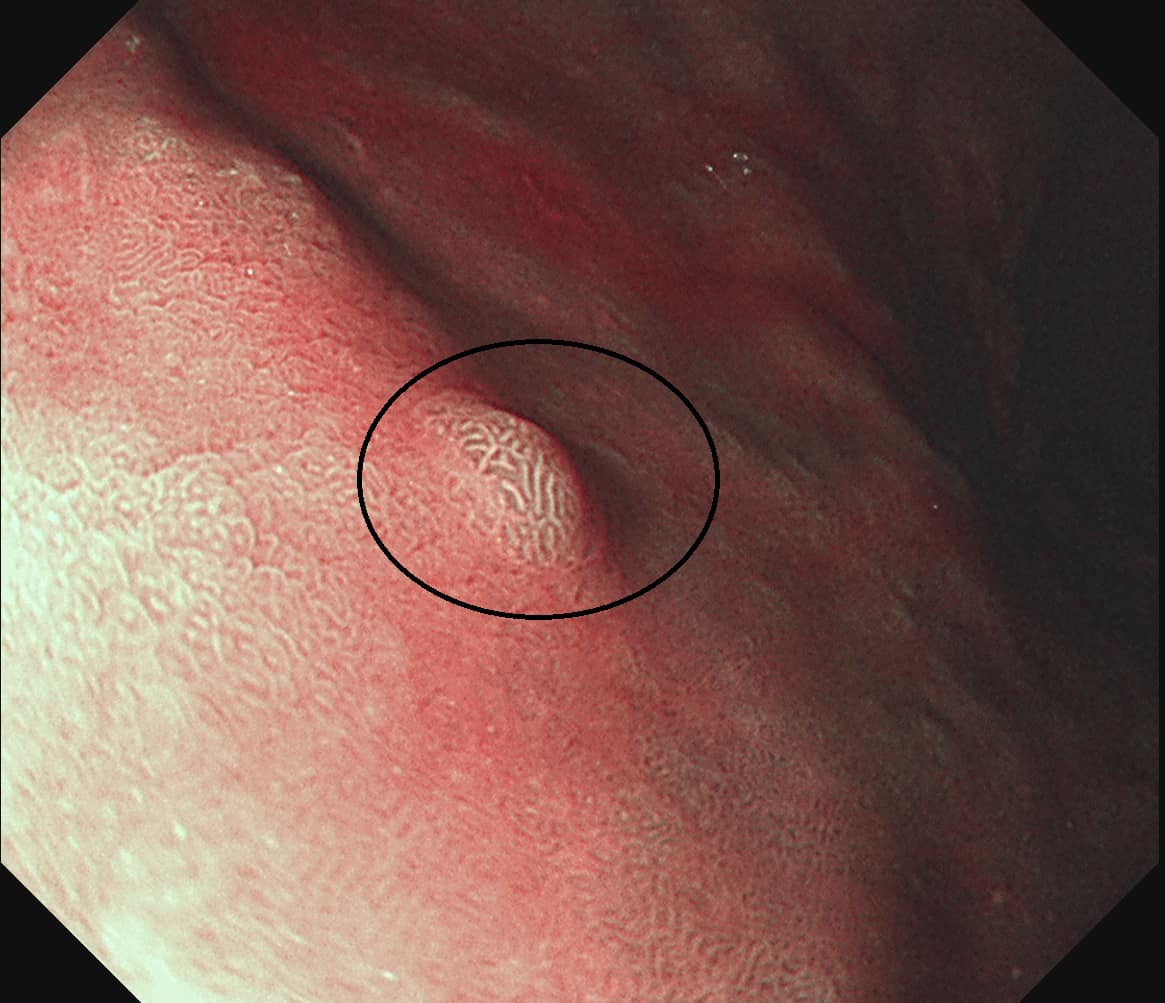

禾馨民權健康管理診所院長林相宏醫師在臉書粉專《胰臟醫師 林相宏 禾馨民權內科診所》分享案例時表示,這名女患者在兩年前做過胃鏡檢查,當時並沒有異常, 這次來定期胃鏡健檢發現胃部除了有明顯的萎縮性胃炎之外,胃壁還有3顆 約0.5公分的隆起,看起來很像單純的胃發炎情況,於是把息肉都切下來化驗,化驗結果是胃部神經內分泌瘤,所幸沒有轉移到其他部分,只要1至2年定期追蹤胃鏡就可以了。

林相宏醫師 授權提供 胃部神經內分泌瘤可能出現的「不典型症狀」包括: